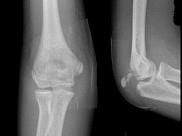

问题 男,6岁,右肘部外伤,结合图像,最可能的诊断是?(?)

选项 A.右肱骨远端骨折 B.右肱骨内上髁骨折 C.右肱骨外上髁骨折 D.右尺骨鹰嘴骨骺损伤 E.右尺桡脱位

答案 D